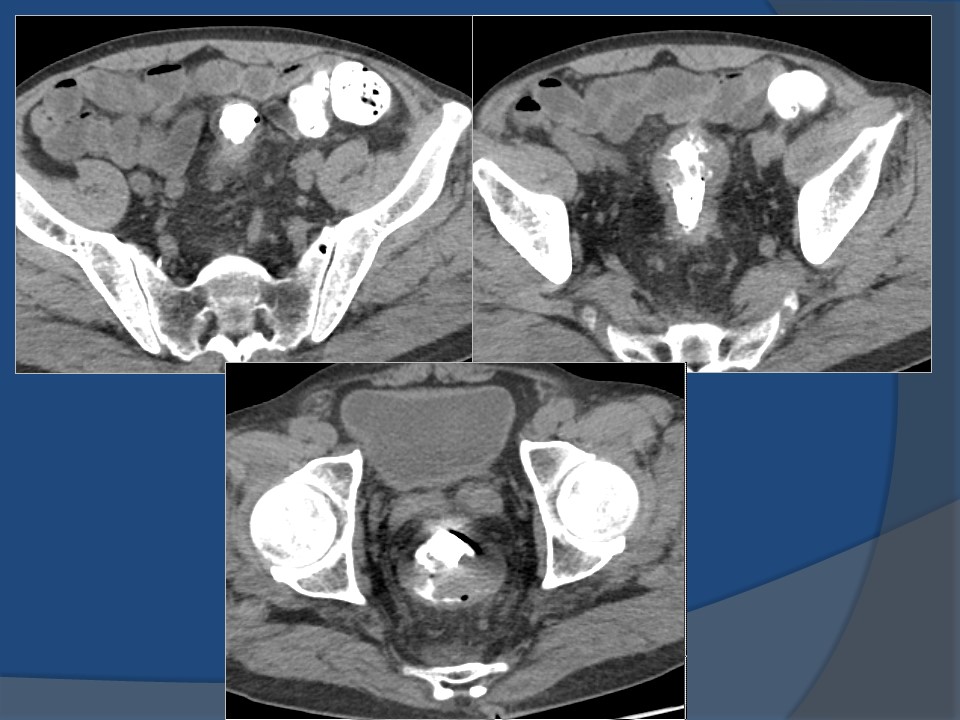

“直肠癌影像表现与分期” 的相关文章